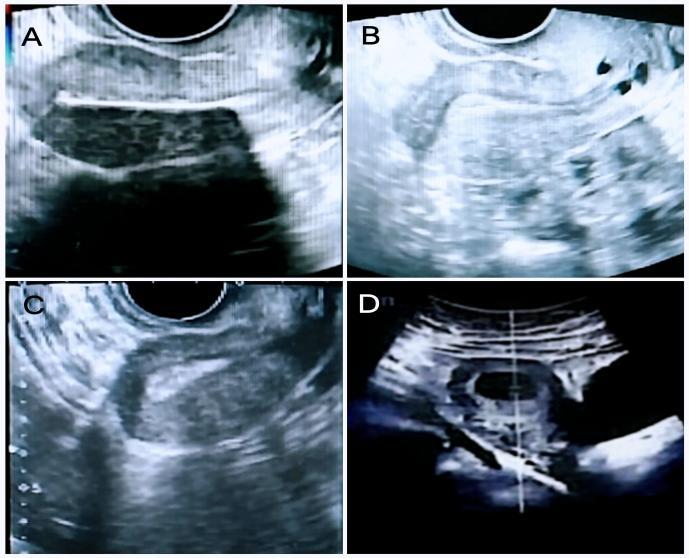

苏州大学附属第一医院三维超声图示

A:PRP宫腔灌注前,内膜3.7mm; B:第一次PRP宫腔灌注后,内膜5.9mm;C:第二次PRP宫腔灌注后,内膜8.6mm; D:PRP结束后4月,确诊宫内孕。